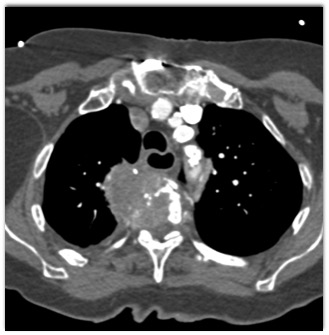

In this patient with back pain and shortness of breath the best dx is?

CTisus Quiz   CTisus Quiz

plasmacytoma

squammous cell carcinoma (SCC)

lymphoma

metastatic renal cell carcinoma